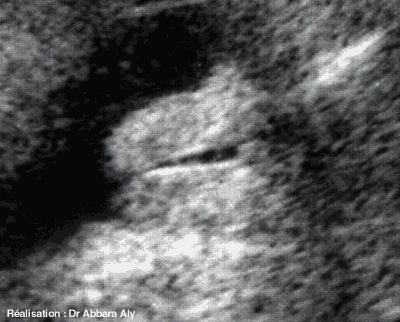

Sexe féminin

l'aspect échographique des organes génitaux externes

féminins chez un fœtus a 32 SA